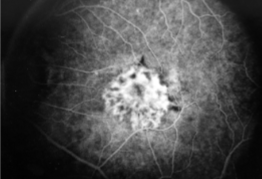

classic CNV

classic & occult CNV

type 2 MNV

MNV is now b/t neurosensory retina & RPE making the IVFA more obvious & well defined

IVFA shows lacy, well-group area of neovascularization

hyperfluorescent early in study

late leakage

lacy early fill of the MNV during the choroidal & arterial filling phase

may have hypofluorescence corresponding to RPE hyperpigmentation & blood in the outline of the MNV

progressive hyperfluorescence throughout the FA w/o leakage of the margins of the MNV